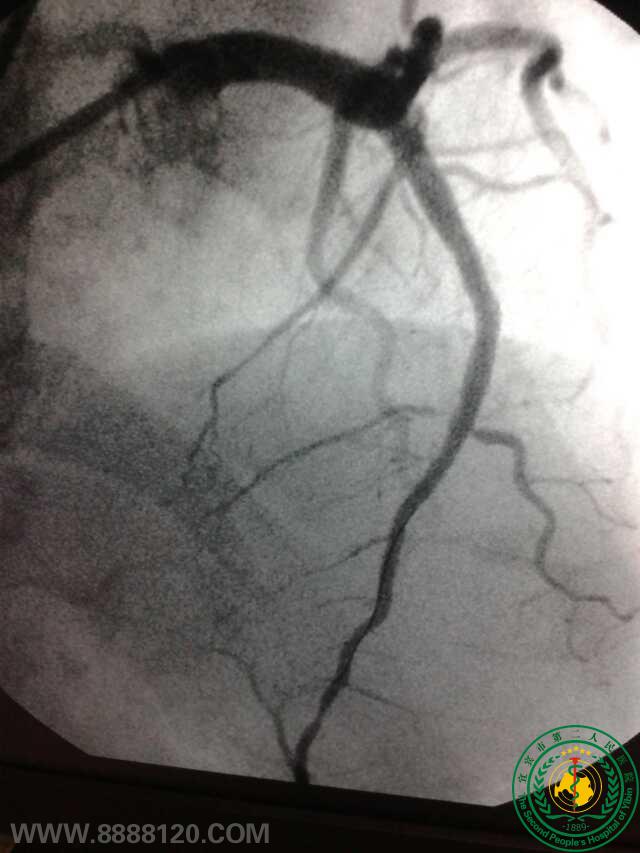

冠脉治疗新技术——宜宾首例冠脉旋磨术

冠脉治疗新技术——宜宾首例冠脉旋磨术6776

宜宾市第二人民医院 图文